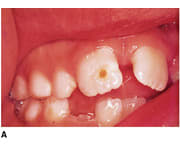

Le patient ci-dessous m'est adressé car ayant un "problème d'émail". Diagnostic ?

Biberon à la grenadine ??

J'aurais aussi pensé à "la carie du biberon"

caries du biberon

les inc inf definitives st "encore" saines mais ça ne va pas durer :sois convaincant ds ta motivation:)